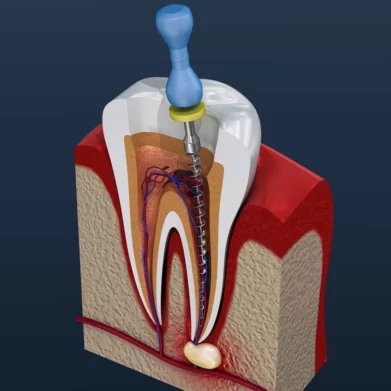

Root Canal

Are you experiencing tooth pain or sensitivity? A root canal procedure can be your savior. Our team of experienced dentists will remove the infected pulp, clean the canal and seal it to relieve pain and save your tooth.

How Modern Endodontics Enhances Smile Confidence